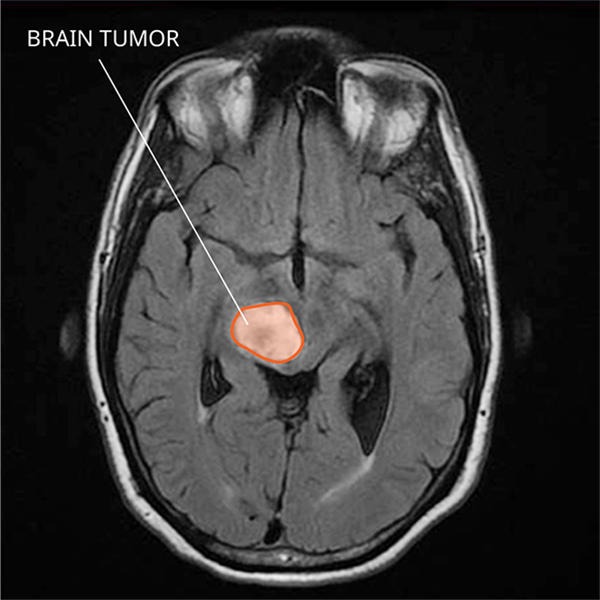

A machine learning model that can detect tumors in MRI brain scans

Can be trained at different medical centers and share the same data

Does not expose patient data, so private information is kept safe